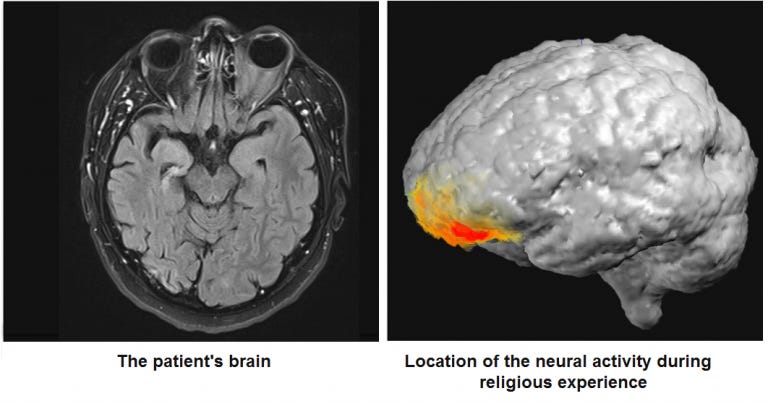

Al revisar el caso, dos científicos ubicaron el origen físico de la 'revelación' en el cerebro:

Durante mucho tiempo se han documentado experiencias religiosas en pacientes con epilepsia, aunque sus mecanismos neuronales subyacentes exactos aún no están claros. Aquí, hemos tenido la rara oportunidad de grabar una conversión religiosa delirante en tiempo real en un paciente con epilepsia del lóbulo temporal derecho que estaba sometido a un video-EEG continuo. En este paciente se produjo una experiencia de revelación mesiánica varias horas después de una compleja convulsión parcial de origen temporal, compatible con la psicosis postictal (PIP). Se analizaron los tiempos del EEG en estado de reposo grabadas por separado para cada una de las bandas de frecuencia convencionales. El análisis topográfico de los tiempos de paso de banda del EEG filtrados reveló una mayor actividad en el rango baja-gamma (30-40Hz) durante la conversión religiosa en comparación con la actividad durante el estado habitual del paciente. El generador del cerebro que subyace a esta actividad se localizó en la corteza prefrontal izquierda. Esto sugiere que la conversión religiosa en PIP está relacionada con los mecanismos de control en los procesos relacionados con el lóbulo prefrontal en lugar de los procesos relacionados con el lóbulo temporal medial.